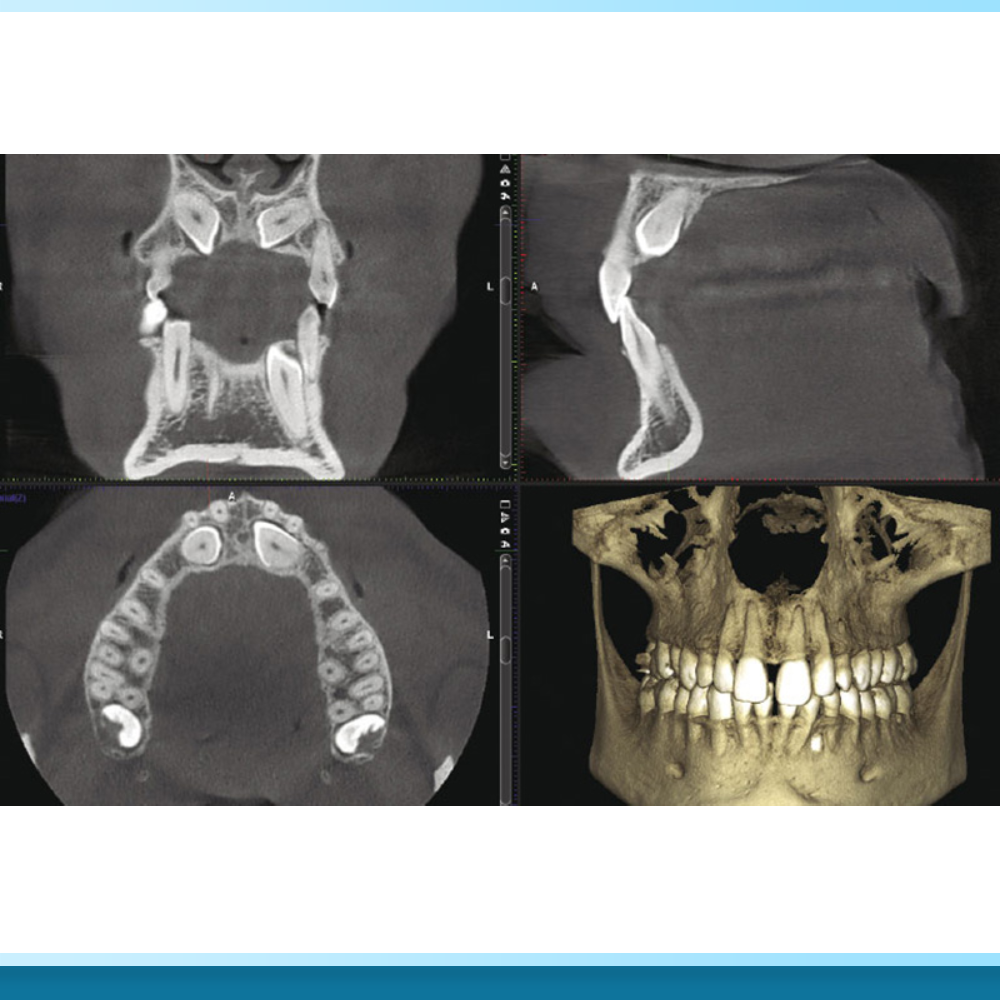

Yếu tố tiên quyết là lựa chọn Nha khoa chuyên sâu Implant. Nơi đây phải có phòng phẫu thuật vô trùng áp lực dương, trang bị máy chụp phim CT ConeBeam để khảo sát xương chính xác.